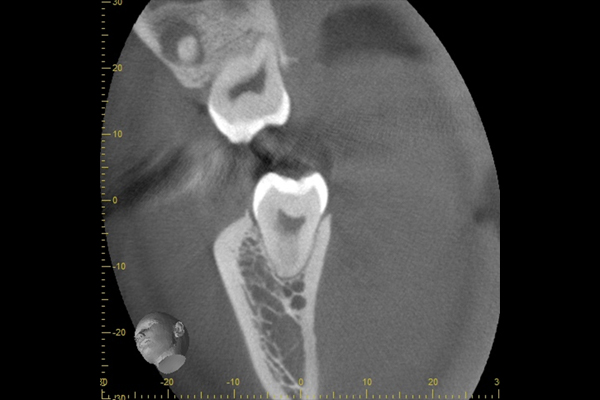

こちらは数年前の私のレントゲン写真です。右上の親知らずが斜めにはえています。お口の中には歯の頭の1部分が見えている状態です。

時々歯茎が腫れて痛かったので、抜いてもらうことにしました。親知らずが上顎洞と接していたため、抜歯後に上顎洞と口腔内が交通しましたが、2週間ほどで塞がりま

ます。